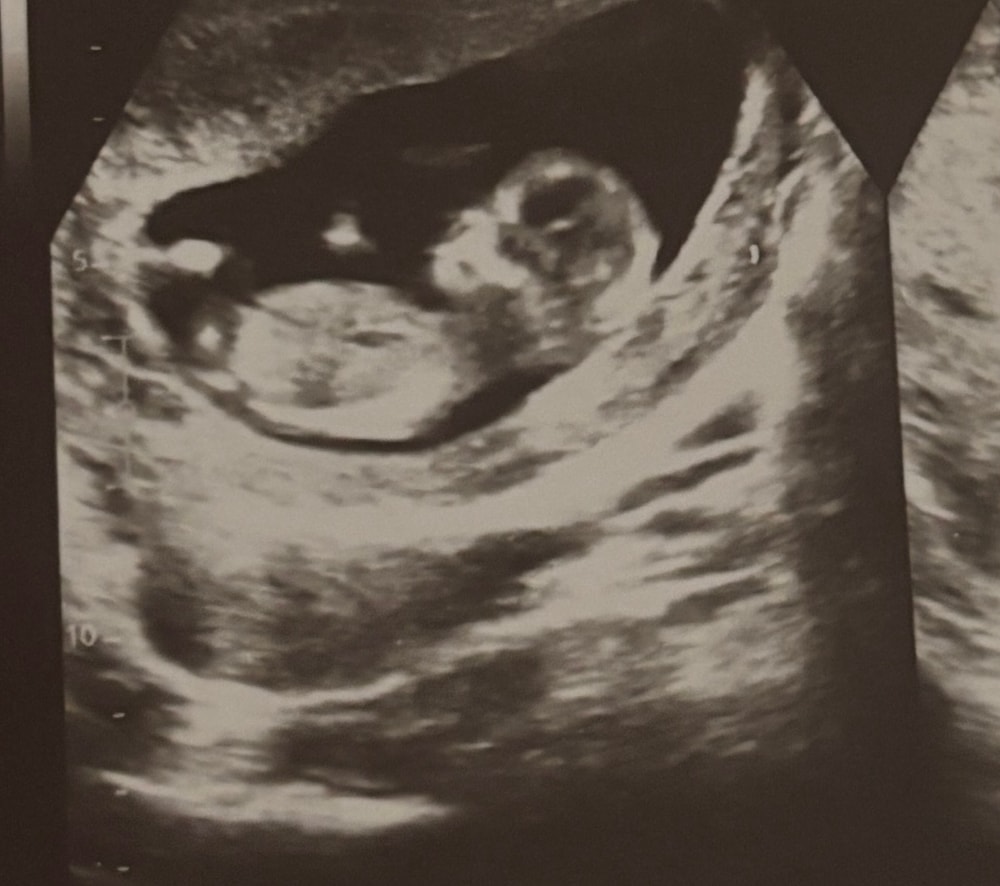

Анастасия в Благополучная беременность месяц Срок 13 недель, как думайте какой пол у ребенка? Пол малыша Врач сделал предположение, хочется послушать еще мнение Посмотрите еще 20 записей на эту тему Отменить Ответить Анастасия Тут не видно бугорок, но интуитивно - девочка ) 24.10.2025 Ответить ИЛИОНА Диагностик Экстрасенс Девочку ждёте 24.10.2025 Ответить Екатерина А мне почему то кажется мальчик 😊 24.10.2025 Ответить mas'ka Я за мальчика) 24.10.2025 Ответить Юлька Конечно, тут пол не видно, но если интуитивно, то девочка 🌹 24.10.2025 Ответить Mommy Юлька, мне тоже так кажется👌 24.10.2025 Ответить Узнали пол! Анализ крови на определение пола Чаты Беременных Выберите чат: Январята-2026 Февралята-2026 Мартята-2026 Апрелята-2026 Майчата-2026 Июнята-2026 Июлята-2026 Августята-2026